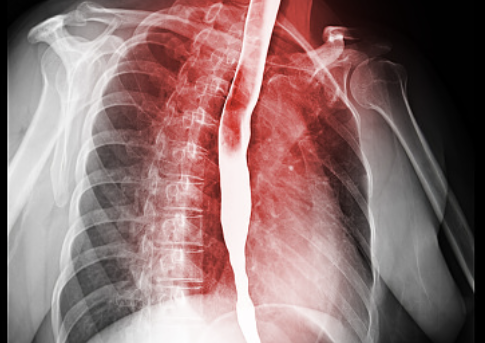

식도염은 식도에 염증이 생기는 병입니다.

위산이나 음식물이 역류하면서 식도가 자극을 받아 염증이 생기게 돼죠.

주로 속쓰림, 가슴 통증, 삼킬 때의 불편함 같은 증상이 나타나고, 심하면 음식을 삼키기가 어려울 수도 있습니다.